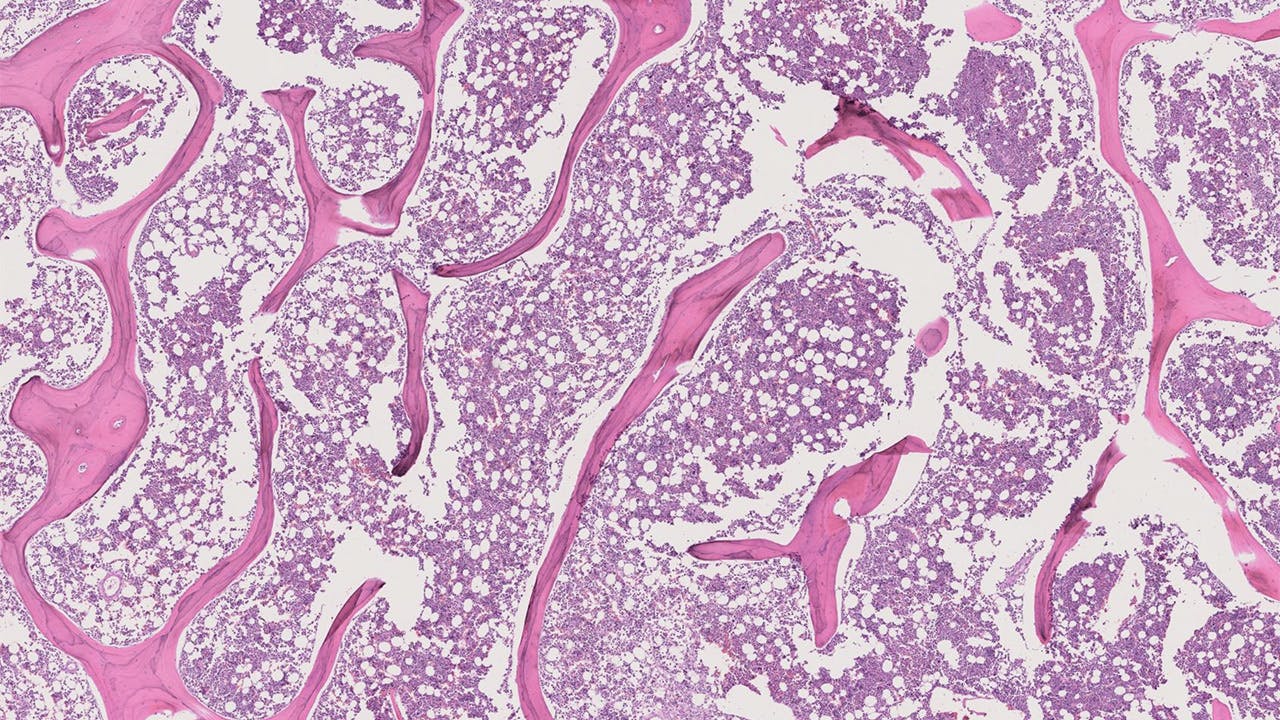

A post-chemotherapy PN calculation helps provide the patient with a prognosis for survival. For example, a PN of 99% indicates that 99% of the tumor is dead, suggesting chemotherapy was effective and the patient has improved odds of surviving. Pathologists calculate PN by looking at, interpreting and annotating whole-slide images (WSIs), which are thinly sliced sections of a specimen (bone tissue, in this context) that are mounted onto slides for microscopic analysis.

First, the team gathered data, including WSIs, from the pathology archives of Johns Hopkins’ U.S. tertiary cancer center. All data came from patients with intramedullary osteosarcoma — that is, osteosarcoma that originated in the center of the bone — who underwent chemotherapy and surgery at the center between 2011 and 2021. The team then had a musculoskeletal pathologist partially annotate three types of tissue on each of the gathered WSIs: active tumor, dead tumor and non-tumor tissue. The pathologist also estimated the PN for each patient. Using this information, the team began to train the model.

After being trained, the model and the musculoskeletal pathologist were given six WSIs to interpret from two osteosarcoma patients. Results showed an 85% positive correlation between the model and the pathologist’s PN calculations and tissue labeling. The model did not always properly label cartilage, which led to an outlier due to an abundance of cartilage on one WSI. When the outlier was removed, the correlation increased to 99%.